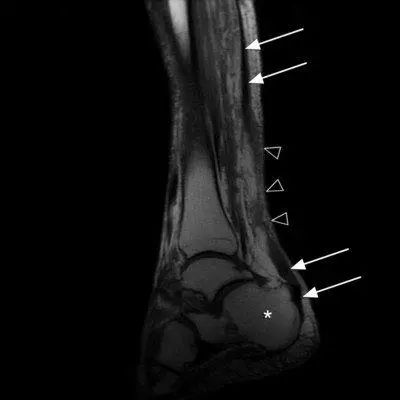

运动医学分析运动损伤案例,运动医学跟腱撕裂

白色箭头是跟腱 三角是断裂处

白色箭头是跟腱的断裂部位